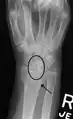

Dynamic instability: Increased scapholunate distance (between yellow lines) upon ulnar deviation of the wrist, but not otherwise.

Dynamic scapholunate instability visible upon clenching the wrist